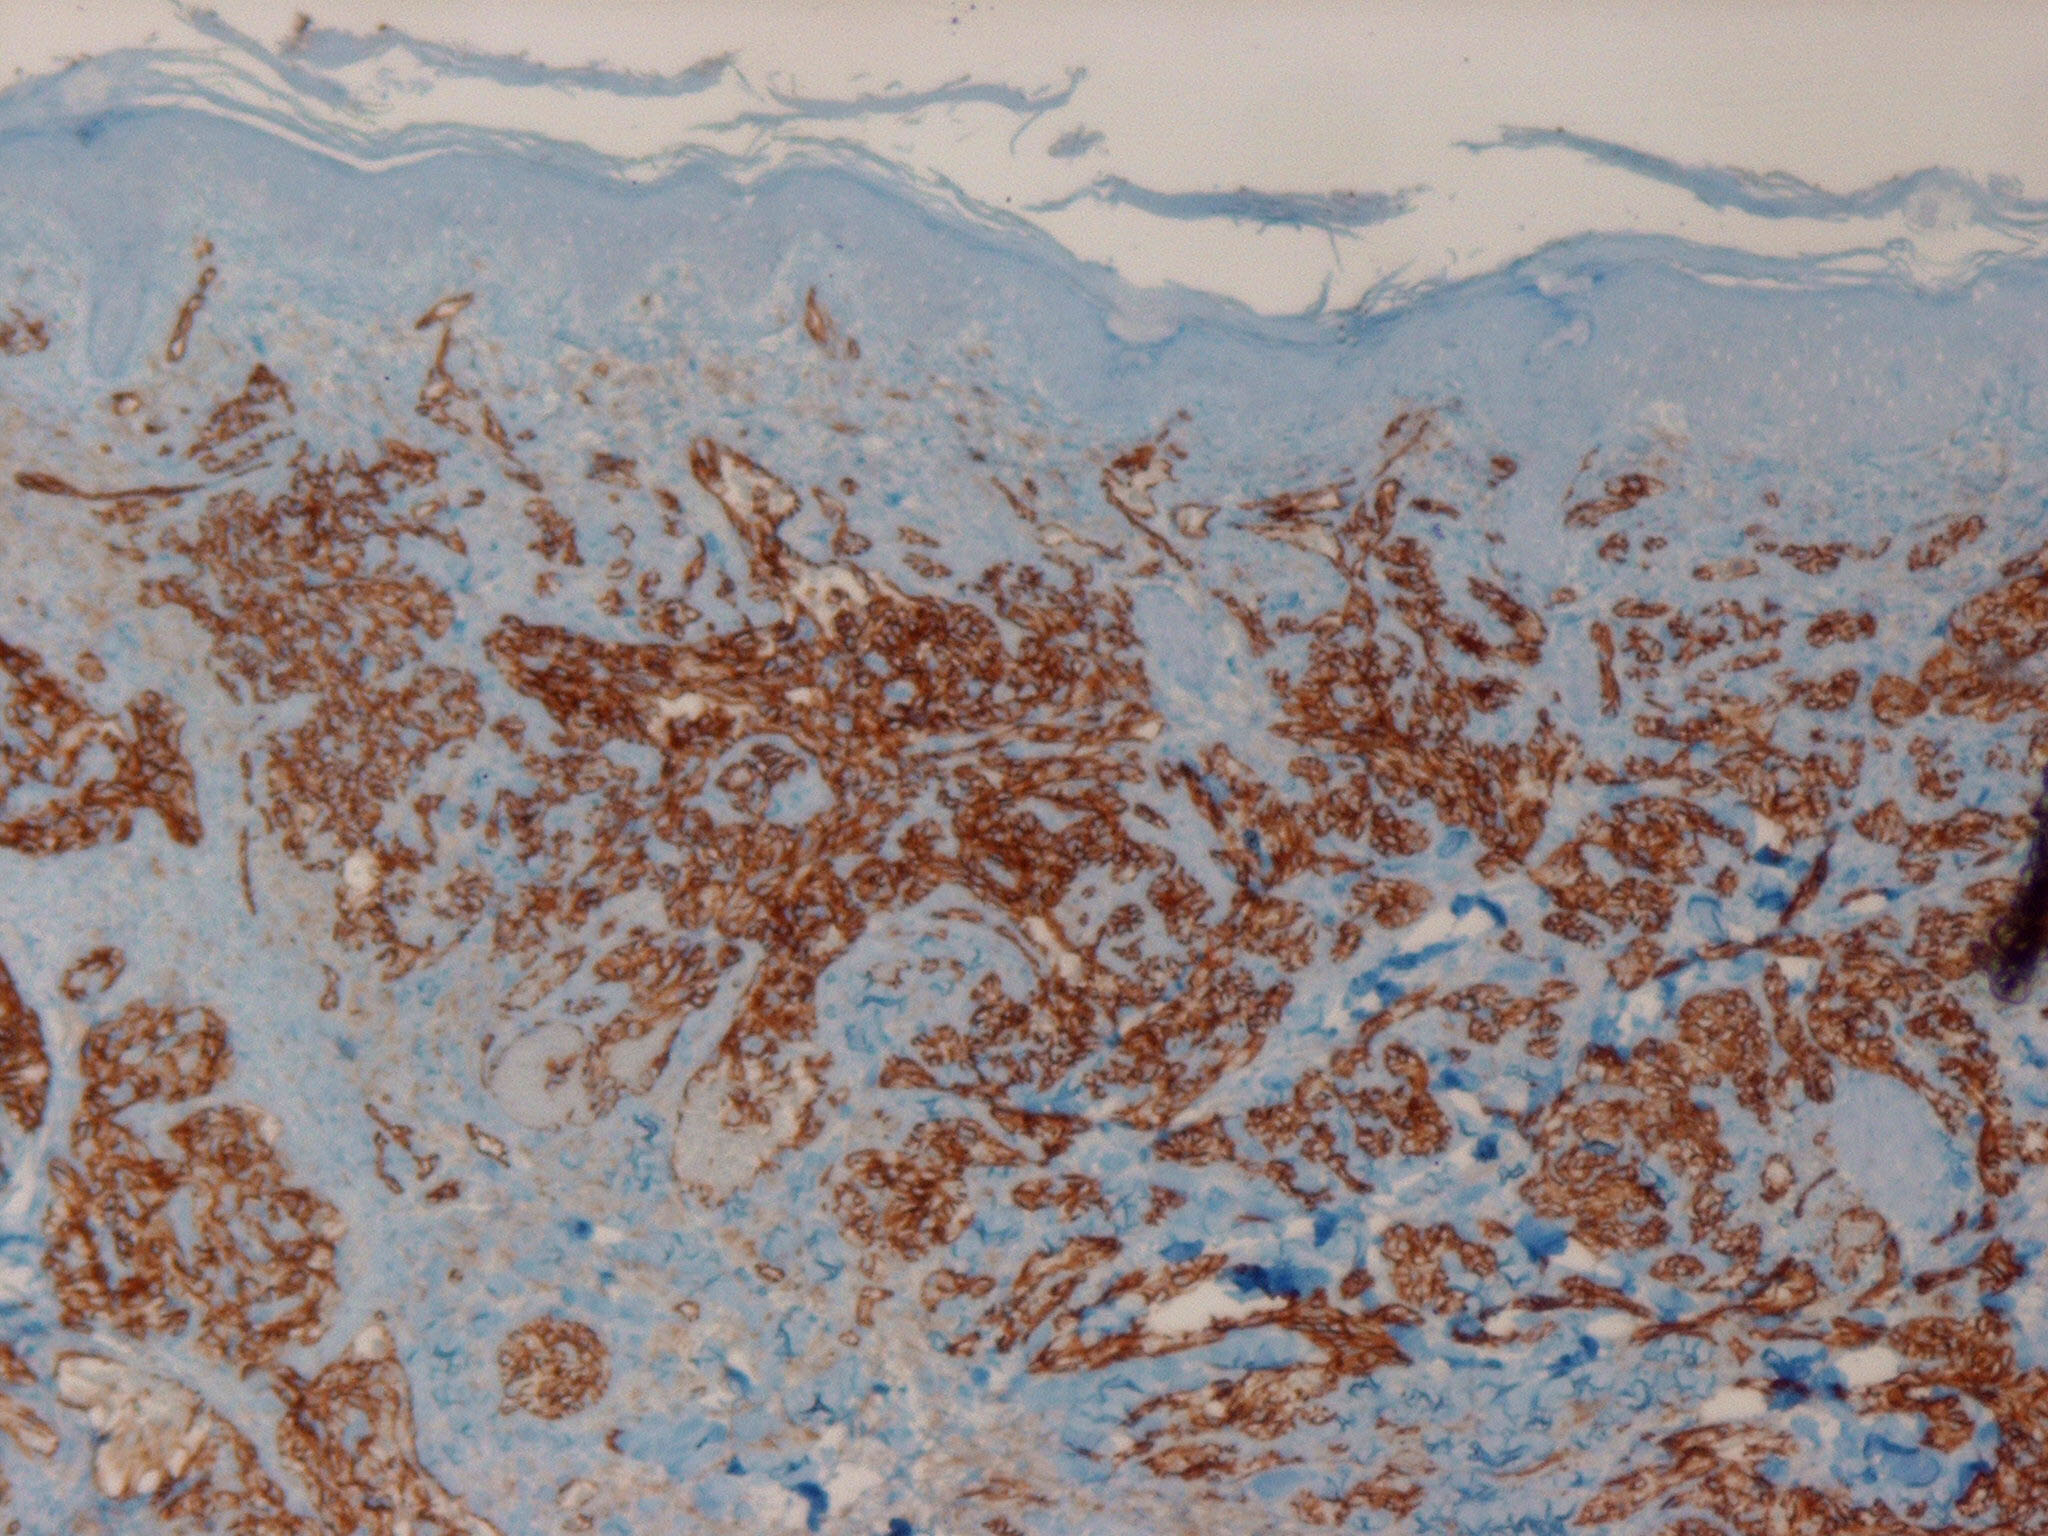

The different clinical variants are indistinguishable histologically and great variability with regard to differentiation of vascular elements can be seen even within individual lesions. Irregular, anastomosing vascular channels lined by endothelial cells with different degrees of atypia and mitotic activity may alternate with areas of closely packed cells with a high mitotic index and sometimes spindle-like morphology . In the latter, less well-differentiated areas and little or no luminal differentiation is present. In particular, in these instances immunostaining for vascular markers such as CD31 and CD34 is helpful for the establishment of the diagnosis.